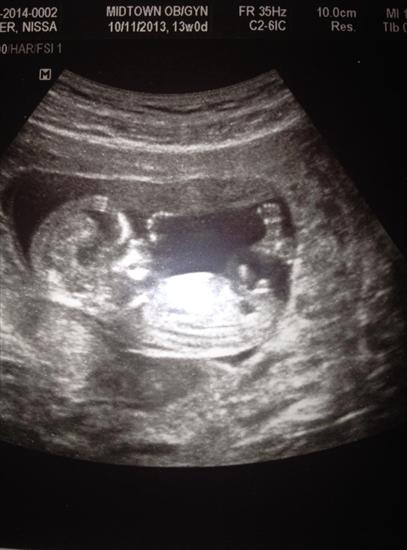

Why are boy nubs all so different from each other?

Hey ladies! Just pondering nubs until my anatomy scan. After seeing so many nubs on the internet, I'm wondering, why do boy nubs differ so much? Girls tend to be all similar: close to the bottom, straight out, some with a fork.

But boys: some are little stacked blobs, some are long straight lines with a bump at the end, some look like hockey sticks or pipes, some stick straight up and some are pretty close to parallel. What the heck? I thought girls were supposed to have the complicated anatomy! Haha.

But here are some examples of what I mean with the different "types":